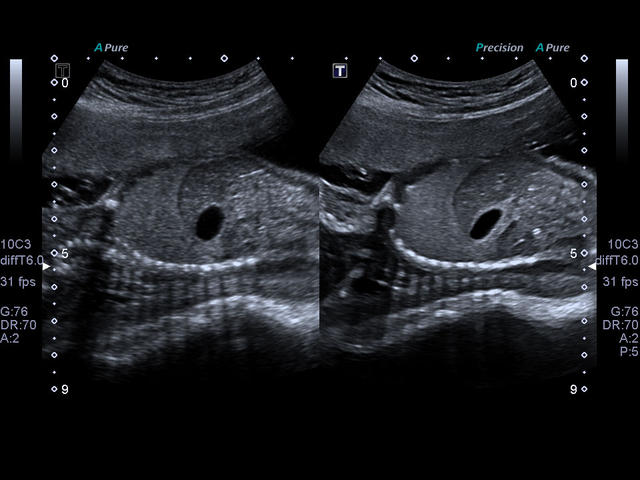

- Акушерство

- Автоматическое измерение воротникового пространства (Auto NT).

- Технология Smart 3D.

- Объемный конвексный

- Автоматическое измерение ТВП плода в режиме 2D: NT